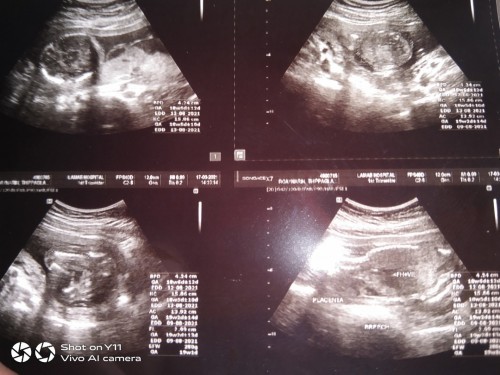

ขอดูภาพอัลตราซาวน์ หน่อยค่ะ ของเรา ทีมลูกสาวค่ะ

18 w ค่ะ ทีมสิงหา แต่ยังไม่รู้เพศเลย